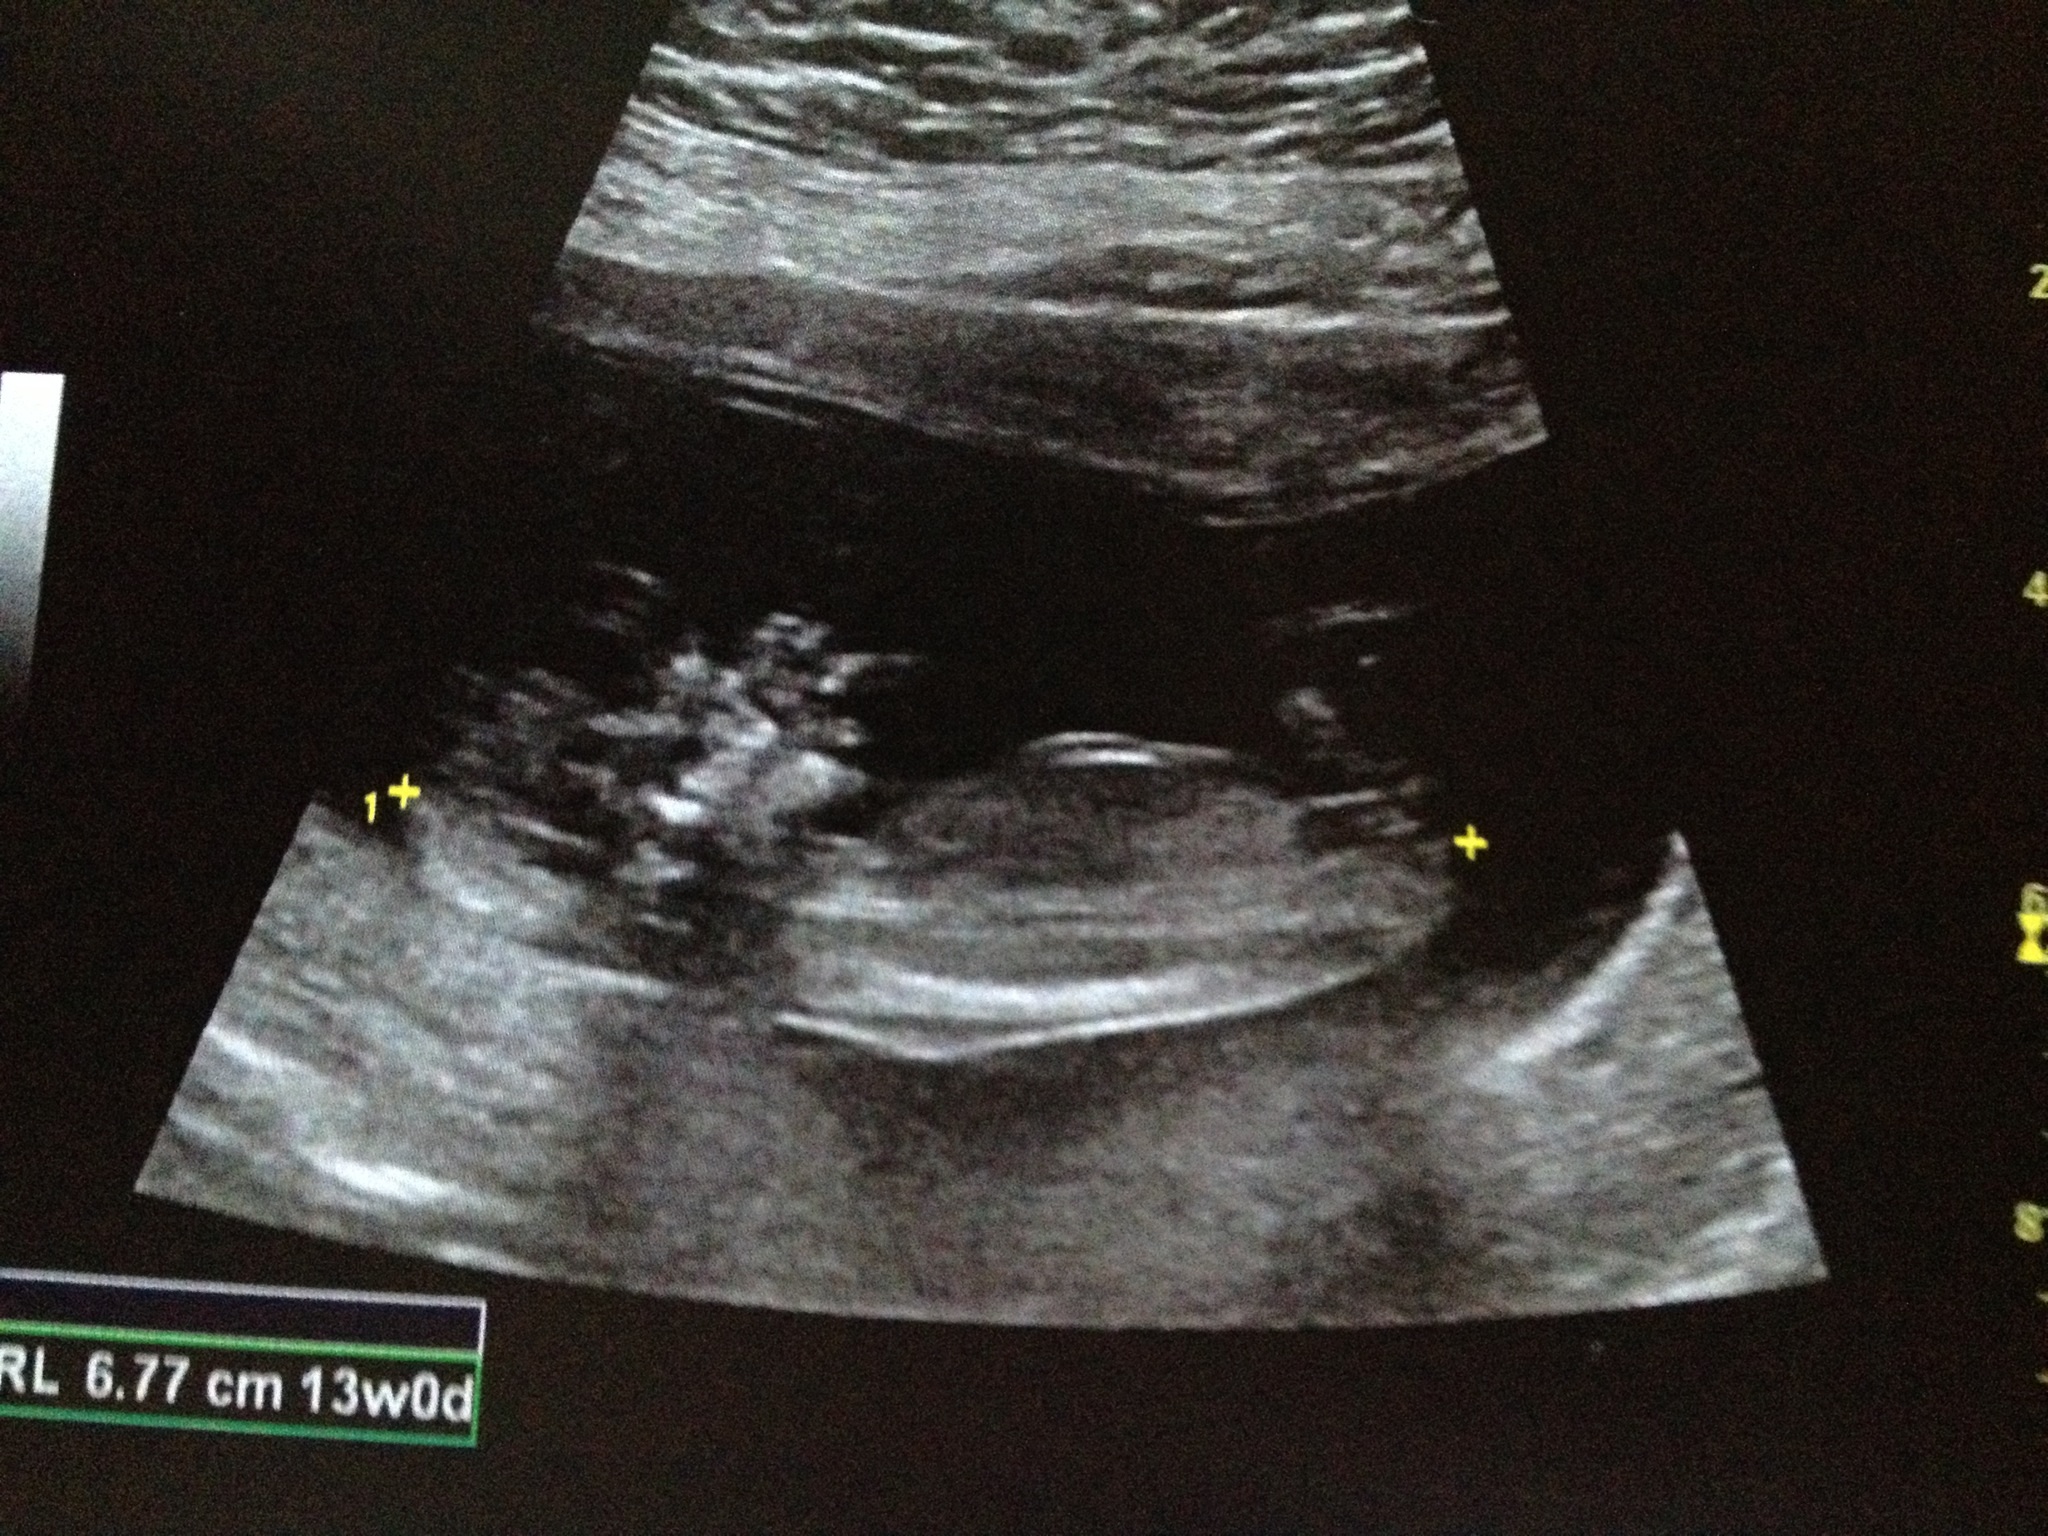

Girl lean. It's a bit more bulbous than I'd like for a classic girl, but at 13 weeks its flat and long. More girly.

The line I long and straight = girl:)

Leaning girl!